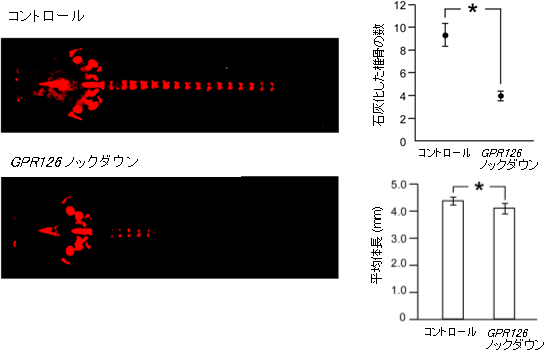

さらに、同研究チームがAISの病変部であるヒトの軟骨や骨、椎間板でのGPR126の発現パターンを調べたところ、軟骨組織で高く発現していることが分かりました。GPR126はヒトの身長や体幹の長さにも関与する遺伝子として知られており、GPR126の機能を欠失させたマウスでは成長障害がみられることが報告されています。さらに、京都大学再生医学研究所 生体分子設計学分野(郭龍研究生、滝本晶研究員、宿南知佐準教授ほか)との共同研究により、GPR126はマウスの脊椎の成長軟骨板の増殖軟骨細胞層に発現すること、GPR126の発現を抑制させたゼブラフィッシュでは、椎骨の骨化が遅延し、体長が小さくなることが明らかになりました(図2)。よってGPR126の異常は、軟骨の形成の障害を通じてAIS発症に関与すると考えられます。

図2 GPR126の発現を抑制させた(ノックダウン)ゼブラフィッシュの骨化の遅延と成長障害

- 左:アリザリンレッド染色による石灰化(赤色)の評価。石灰化とは、カルシウムが沈着して正常な骨ができていることを示す。コントロール(正常)に比べてGPR126の発現を抑制させたゼブラフィッシュでは、石灰化が非常に少ない。

- 右上:石灰化した椎骨の数。

- 右下:平均体長。GPR126の発現を抑制させたゼブラフィッシュでは明らかな椎骨の骨化の遅延(染色性の低下)と成長障害がみられる。